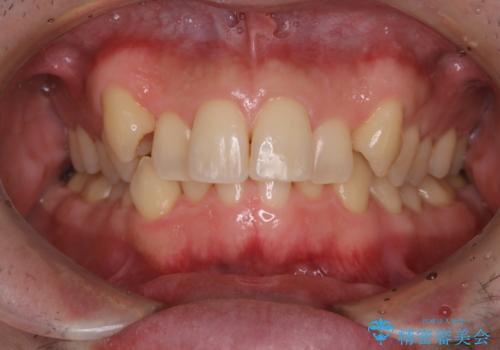

タバコのヤニをPMTCできれいに

- タバコによる着色が気になるため、全て取りたいとのことで来院されました。PMTC60分コースを行いました。

PMTCは、歯に付着した汚れを除去していくため、着色が気になる場合にも行うことができます。ご自身でのセルフケアだけで着色を落とそうとすると、逆に歯を傷つけてしまったり、精密に汚れを除去できないこともあります。また、日常生活で着色しやすい飲食物を避けたりすることはストレスに感じてしまったり、あまり現実的ではありません。

歯科医院にて、適切な処置を行うことで、長期的に安定したお口の環境が作られます。まずはカウンセリングなどもおススメです。